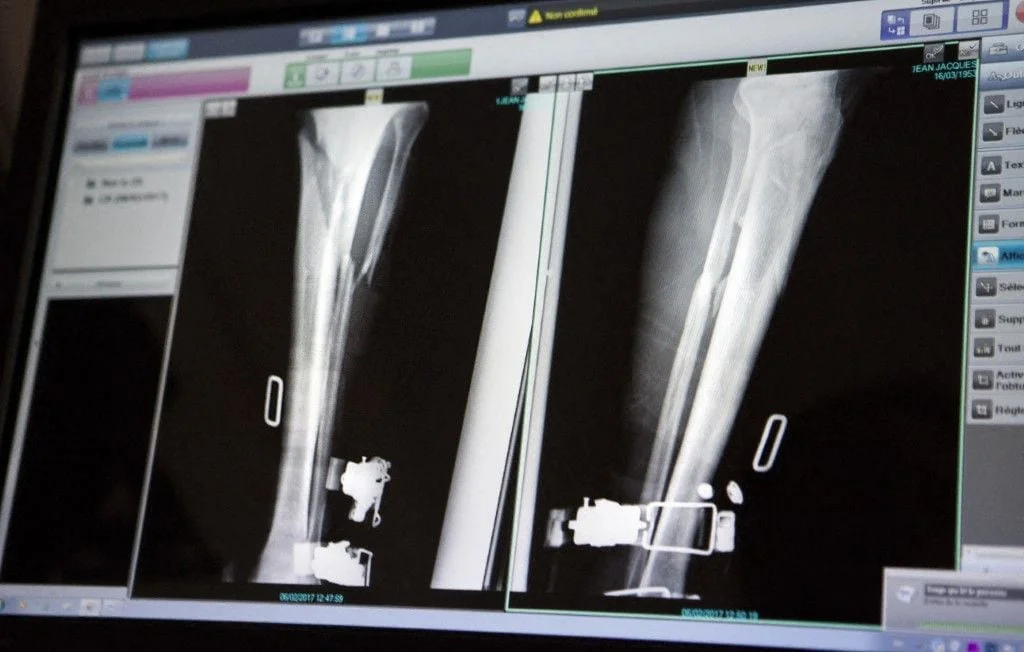

Chaque année, bien que rares, des erreurs médicales graves surviennent dans les établissements hospitaliers. En décembre 2021, un retraité septuagénaire a été victime de l’une d’entre elles à l’hôpital de Lisieux, dans le Calvados. Après une chute qui a entraîné une fracture de la jambe gauche nécessitant une opération et la pose d’une broche, son intervention chirurgicale a malheureusement été entachée d’une erreur.

En effet, le patient a découvert, à son réveil de l’anesthésie, qu’un pansement recouvrait sa jambe droite, alors que c’est la jambe gauche qui devait être opérée. Ce n’est qu’une heure plus tard que la bonne jambe a été finalement prise en charge chirurgicalement. Le septuagénaire témoigne : « J’ai deux broches, une dans chaque jambe ». Plus de trois ans après cet incident, il continue de ressentir des douleurs persistantes à la jambe droite, celle qui n’aurait jamais dû subir l’opération, et rencontre des difficultés à la marche.